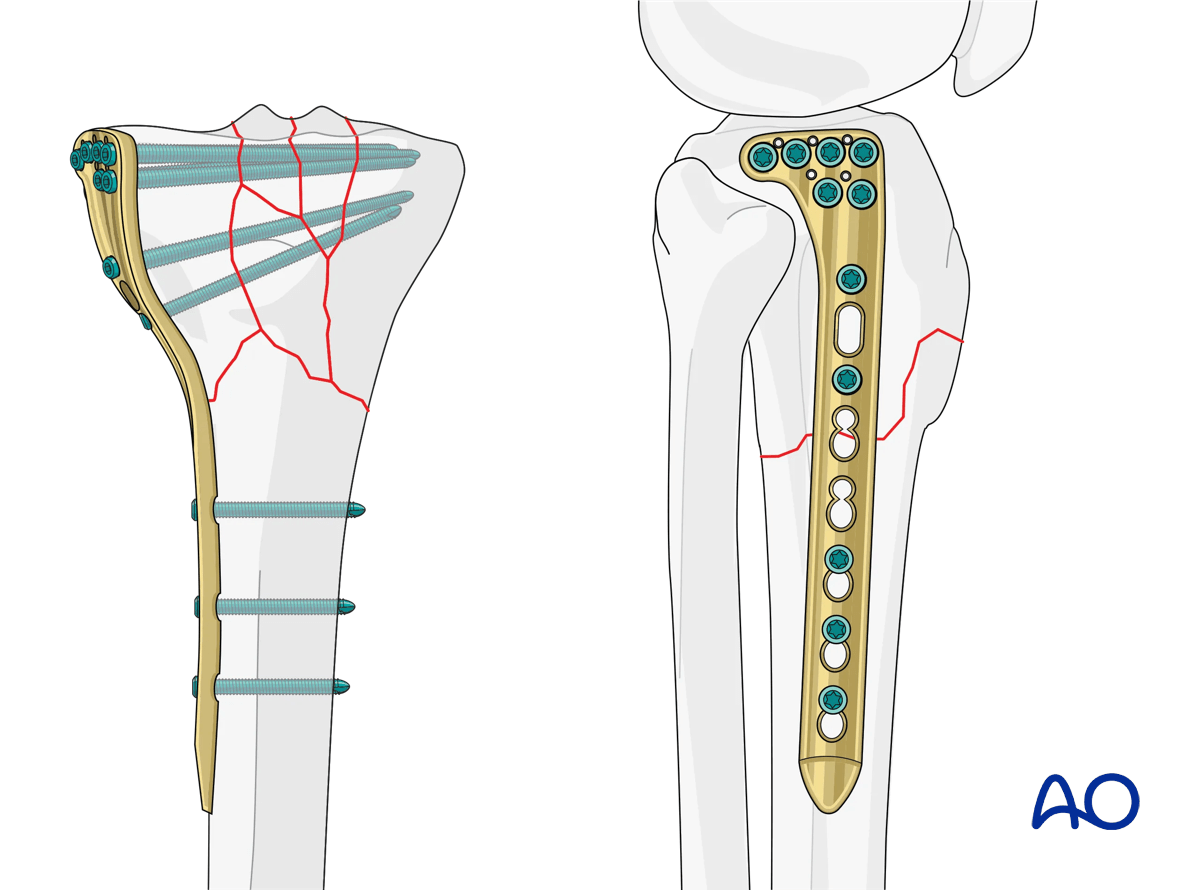

Plate length

When using a bridge-plating technique, which assumes that there is comminution that will be indirectly reduced, the plate length should be approximately three times the length of the zone of comminution, balanced on either side of the fracture area. In the vast majority of instances, however, the comminution is located in the proximal portion of the tibia. Therefore, a general concept is that the distal portion of the plate at least equals the length of the zone of comminution, preferably ending at least at the junction of the middle and distal third of the tibia, with a minimum of 2-3 screws. The screw density in this distal segment should approximate 2.5 screws.

Proximally, given the fact that we cannot take advantage of plate length because of the proximity to the articular surface, the screw density should be increased maximally.

A preoperative x-ray planning template is useful in determining the length of the plate and the position of the screws.

Proximal tibia fractures – planning plate length

Positioning of the plate

Ideal positioning of the plate depends on several factors. The plate should allow proper fixation of all components of the fracture including the articular segment, and have enough fixation, both proximally and distally. The plate should closely fit the proximal meta-epiphysis to minimize plate prominence.

When inserting screws from lateral to medial the anatomy of the plateau must be taken into consideration in order to avoid penetrating the concave medial joint surface.

7. Finalized reduction and screw placement

At this point, any articular surface reduction should have been completed. Any residual translational or angulatory malreductions can now be improved using the plate as a guide for reduction. This can be performed using clamps, or push-pull screws through the plate. In some situations, a full-length plain x-ray is advisable to ensure alignment. Screw placement depends on the type of fracture. The positions of the locking head screws should be chosen in accordance with the established biomechanical principles for internal fixation. The locking head screws should be inserted remote from the fracture gap in the main diaphyseal fragment. Three to four plate holes in the region of the fracture zone should remain free of screws to ensure sufficient elasticity of the construct.

Proximal tibia: complete articular fracture - Angular stable plating – finalized reduction and screw placement